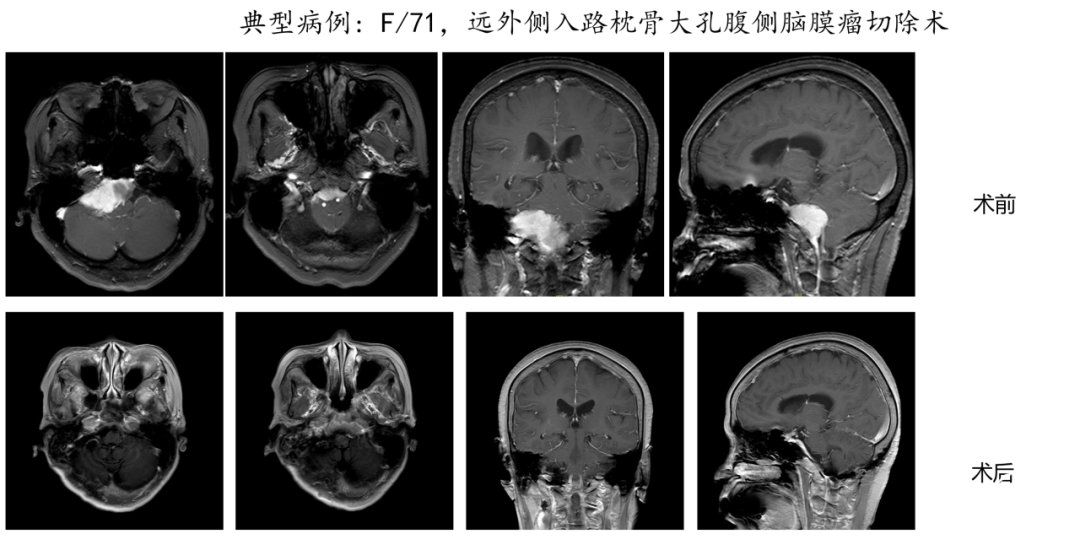

“双镜联合”是一种先进的神经外科手术技术,它结合了显微镜和神经内镜的优势,旨在更安全、更精准地切除位于颅底复杂区域的肿瘤,这是我科近几年开展的院内新技术,这种手术方法在处理如岩斜区、海绵窦区、枕骨大孔区、颈静脉孔区等难以到达且手术风险高的区域时,具有显著的优势。